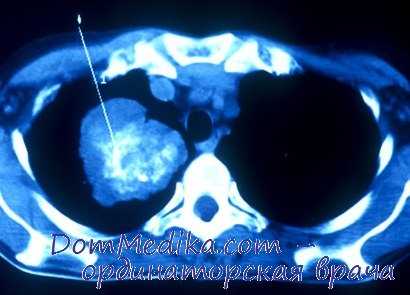

Компьютерная томография рака легкого

КТ — основной метод визуализации при диагностике рака легкого после выполнения рентгенографии органов грудной клетки в прямой проекции. Всем пациентам, за исключением агонирующих, следует провести КТ органов грудной клетки верхних отделов брюшной полости с контрастным усилением. Описание КТ необходимо учитывать при определении стадии заболевания.

КТ следует выполнить при первой же возможности, до каких-либо инвазивных процедур. Это нужно для сокращения методов диагностики, получая от них (например, от бронхоскопии) максимальную пользу.

Позитронно эмиссионная томография при раке легкого

ПЭТ — вид визуализации метаболических процессов, основанный на способности злокачественных клеток захватывать меченную радиоактивной меткой глюкозу. В качестве метки при раке легкого используют 5-фтордезоксиглюкозу (5-ФДГ), которая, в отличие от обычной глюкозы, фосфорилирована и не метаболизирует-ся опухолевыми клетками. Это позволяет получать изображение в соответствии с интенсивностью захвата 5-ФДГ клетками. ПЭТ с 5-ФДГ — неспецифичный метод, поскольку изотоп будет захватываться при многих воспалительных заболеваниях.

Применительно к раку легкого это означает, что ложноположительные результаты могут давать такие заболевания, как туберкулез, саркоидоз и другие гранулематозы в качестве воспалительных причин вну-тригрудной лимфаденопатии, так же, как и вторичные пневмонии, наблюдаемые при раке легкого. В настоящее время для получения точной анатомической корреляции зон накопления 5-ФДГ ПЭТ обычно совмещают с КТ. Характерная картина ПЭТ-КТ представлена на рис. 13-10. ПЭТ-КТ обладает большей чувствительностью и специфичностью по сравнению с обычной КТ, поскольку позволяет оценить увеличенные внутригрудные лимфатические узлы и может определить метастазы приблизительно у 10% пациентов, которым, в целом, возможно выполнить радикальное лечение.